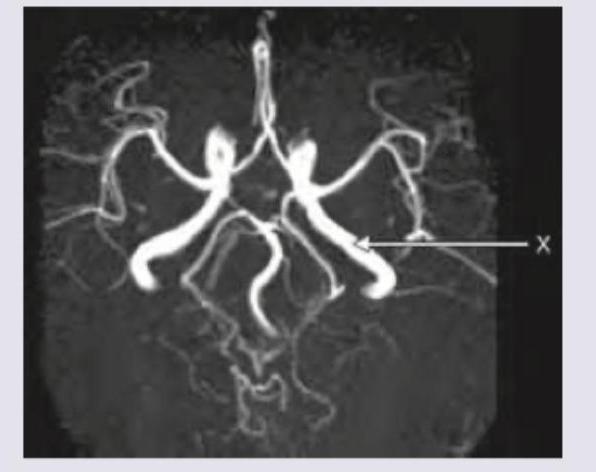

The blood vessel marked as $X$ in the CT angiography image is:

Explanation: ***P2 PCA*** - The image displays a CT angiography of the **Circle of Willis**. The vessel marked 'X' is a segment of the **posterior cerebral artery** (PCA). - The PCA is conventionally divided into four segments: P1 (pre-communicating), P2 (peduncular), P3 (quadrigeminal), and P4 (cortical). The 'X' points to the segment of the PCA that is distal to the posterior communicating artery, indicating the **P2 segment**. *P1 PCA* - The **P1 segment** of the PCA is the initial part, located between the basilar artery bifurcation and the posterior communicating artery. - The vessel marked 'X' is clearly **distal to the connection point** where the posterior communicating artery would typically join, thus it is not the P1 segment. *Internal carotid artery* - The **internal carotid arteries** typically ascend higher and give rise to the anterior and middle cerebral arteries, forming the anterior circulation. - The vessel marked 'X' is part of the **posterior circulation**, originating from the basilar artery system, not the internal carotid artery. *M1, Middle cerebral artery* - The **M1 (main trunk) segment of the middle cerebral artery** extends laterally from the internal carotid artery. - The vessel marked 'X' is situated more posteriorly and medially, clearly identifying it as part of the **posterior cerebral artery**, and not the middle cerebral artery.